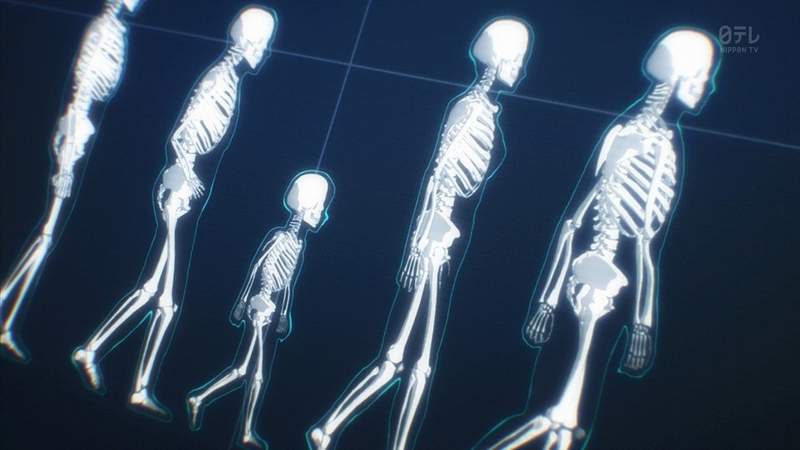

你們有拍過X光吧?相信現在在螢幕前面99%的人在成長過程中都一定多少拍過X光片,每次在做檢查之前醫護人員都會告知一些注意事項,像是不能戴手鍊、項鍊、手表等等的,連美甲或是耳環也要卸掉。大多數人都會乖乖遵守,但是你們有想過如果不這麼做的話又會發生什麼事情呢?

日前日本網友やすいやさん就在推特 (@ny1069p) 上分享了自己的經歷,他表示最近因為老婆手骨折,於是帶著她去拍X光,不過她卻忘記在拍之前卸掉美甲,想不到拍出來的片子卻讓醫生和他們都一秒爆笑……美甲們居然都入鏡啦!

不過因為照片中的美甲圖案做得太精緻,網友們紛紛留言:「第一次看到這麼可愛的X光片呢!」、「美少女戰士!」。

不得不說這畫面真的讓人完全忘記自己在看的是X光片,大家未來如果有要去檢查的話一定要記得卸掉,避免憾事發生唷!